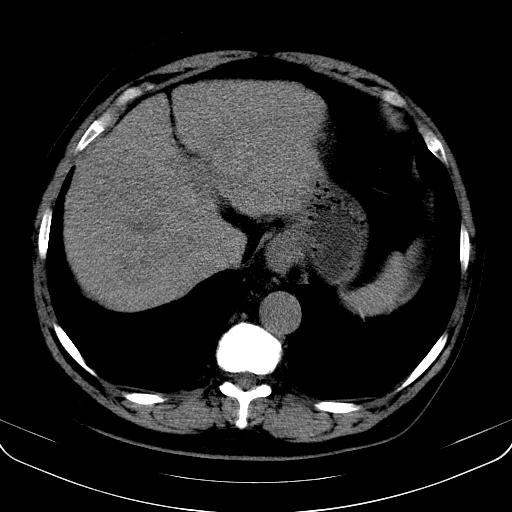

以下是引用jia119在2008-3-5 13:31:00的发言:[br]肝内多发片状低密度影,密度不均,我还是考虑肝ca可能,另肝内小囊肿,胆囊增大。

以下是引用形影不离在2008-3-5 12:18:00的发言:[br]肝硬化伴门脉高压征,肝内占位待排,增强再说.

以下是引用随光逐影在2008-3-5 21:11:00的发言:[br]肝硬化伴门脉高压(食管下段静脉曲张),肝癌不排除。建议:行ct增强扫描检查。

以下是引用同在2008-3-5 13:56:00的发言:[br]考虑肝癌可能性大,胆囊增大.